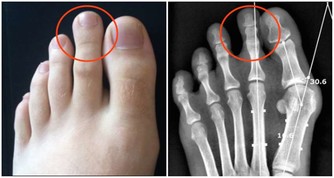

6. 早期飢餓導致虛弱、肌肉損失和脫髮

斷食超過48小時後,可能有一些相當嚴重的後果。

比如虛弱和疲勞,這可能導致你暈倒;肌肉損失;

骨密度降低,導致骨骼非常脆弱;

心臟肌肉減弱引起的心臟問題;血壓降低;

潰瘍以及由於循環不暢而出現的並發症;

感覺很冷;嚴重脫水導致腎衰竭;脫髮嚴重。